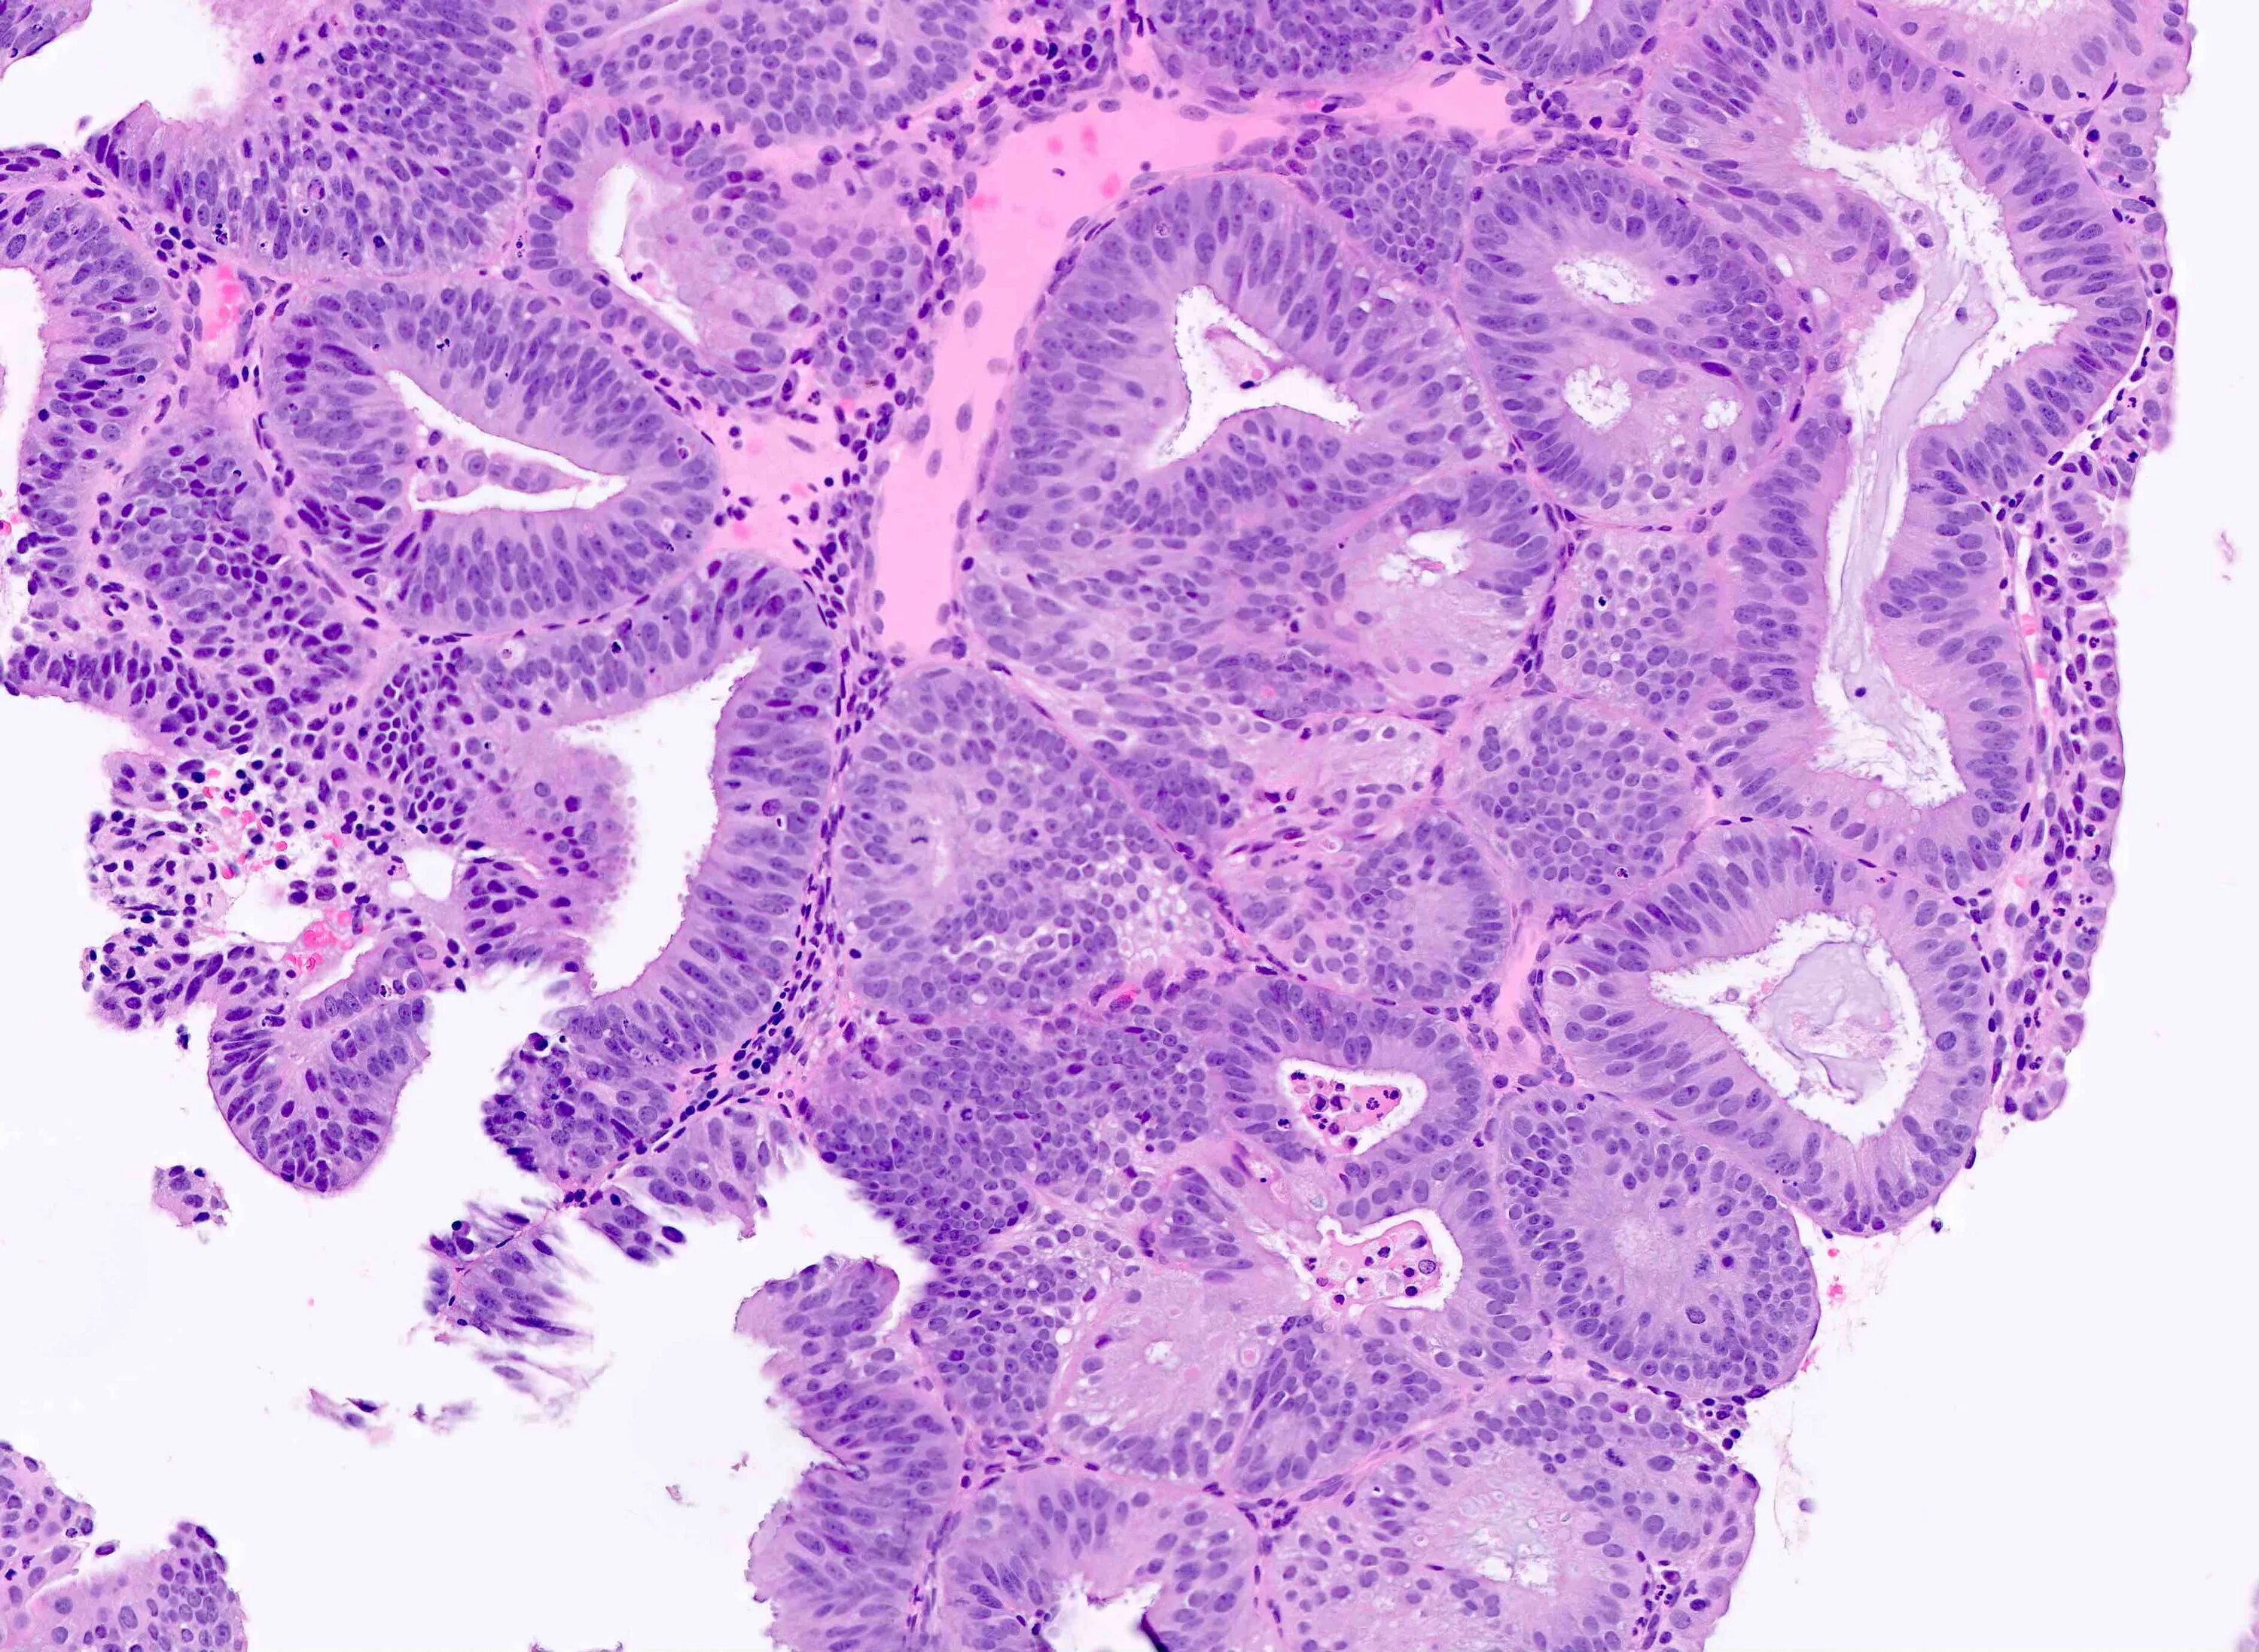

Высокодифференцированная аденокарцинома кишки